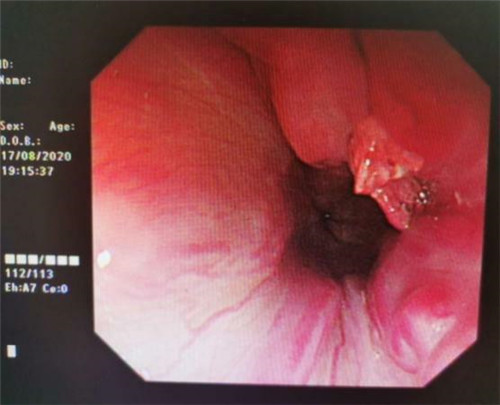

手术中,在镜下发现数条食管静脉曲张延伸至胃底,胃腔内有大量新鲜红色血液及血凝块,寻找到出血部位时仍在向外渗血,血压持续下降,患者时刻有生命危险。曹鹏副主任当机立断对曲张静脉破口处进行组织粘合剂及硬化剂注射,并对曲张静脉进行套扎治疗,在麻醉师陈琦的保驾护航下,整个过程不到半个小时,为患者成功止血,患者转危为安。